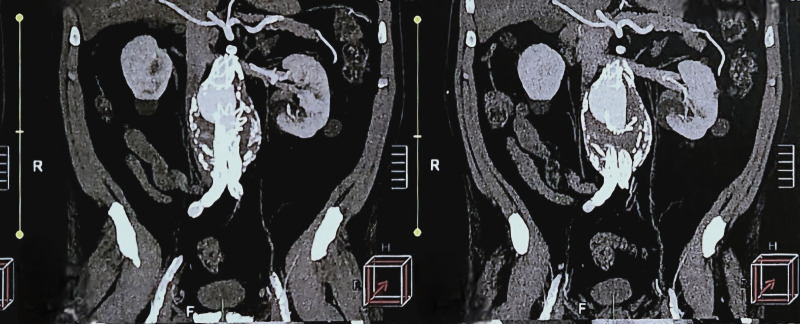

III型内漏的特点是内接枝结构出现问题,如金属结构断裂、分离或破裂。它们是一种罕见的并发症,在经血管内修复治疗腹主动脉瘤的患者中发生率为2.1%,在第一代和第二代内移植物中发病率较高,可早发生(30天后),也可晚发生。这种类型分为IIIa -组件模块化分离-和IIIb -涉及内移植物的网状骨折或破裂。本病例报告描述了一位无症状的患者,他之前接受了肾下腹主动脉瘤修复术,并在随访的计算机断层扫描中发现了一个IIIa型内漏,主体与近端延伸分离。进行第二次血管内介入以封闭腔内渗漏并矫正动脉瘤。

Type III endoleaks are characterized by a problem with the endograft structure, such as fracture of the metallic structure, separation, or rupture. They constitute a rare complication, occurring in 2.1% of patients after treatment of abdominal aortic aneurysm by endovascular repair, with higher incidence in first and second generation endografts, and can occur early (after 30 days) or later. This type III classification is subdivided into IIIa -modular separation of components - and IIIb - mesh fracture or rupture involving the endograft. This case report describes an asymptomatic patient who had previously undergone infrarenal abdominal aortic aneurysm repair and underwent follow-up computed tomography which found a type IIIa endoleak with separation of the main body from the proximal extension. A second endovascular intervention was performed to seal the endoleak and correct the aneurysm.